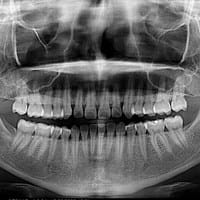

Extracción de muelas es necesario?

Mi duda o mi "preocupación" es si al hacer un tratamiento de ortodoncia es necesario la extracción de las muelas de juicio. Hace poco fui al dentista y me mando que me hiciera una radiografía, mis muelas del juicio me están saliendo como acostadas,...